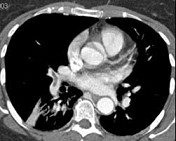

- 单项选择题男,56岁, 食管癌术后,胸痛, 呼吸困难,结合CT图像, 最可能的诊断是 ( )

B、肺栓塞